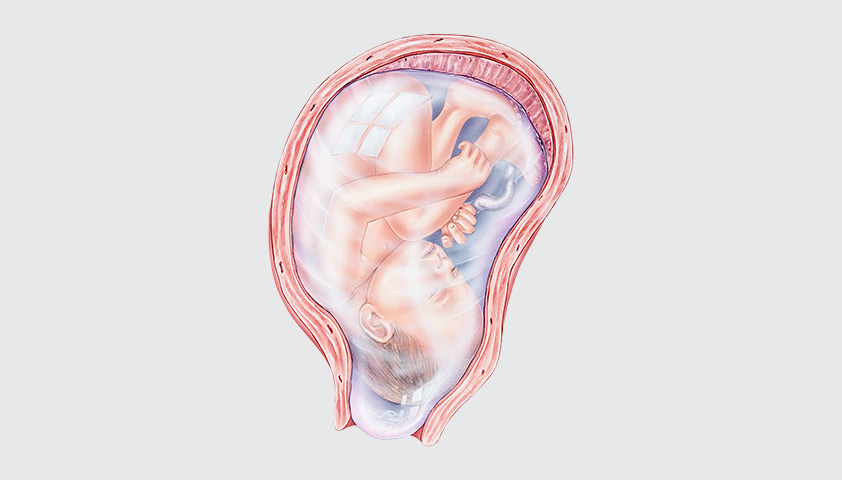

Медицинские аспекты мекония в околоплодных водах